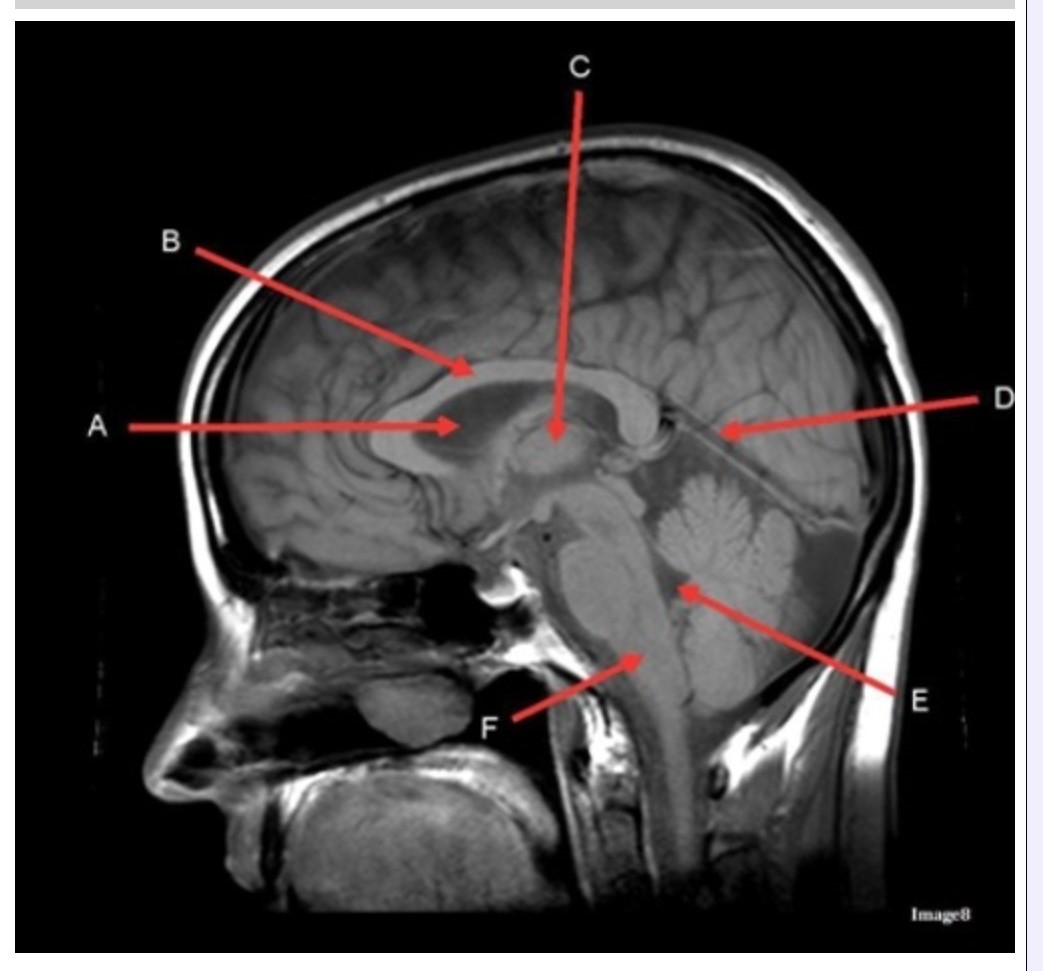

Letter C in Image 8 is pointing to:

A. Tentorium

B. Corpus callosum

C. Thalamus

D. Fourth ventricle

E. Medulla oblongata

Letter F in Image 8 is pointing to:

A. Tentorium

B. Cerebellum

C. Thalamus

D. Fourth ventricle

E. Medulla oblongata

Letter A in Image 8 is pointing to:

A. Tentorium

B. Corpus callosum

C. Hypothalamus

D. Fourth ventricle

E. Lateral Ventricle

Letter E in Image 8 is pointing to:

A. Tentorium

B. Cerebellum

C. Thalamus

D. Fourth ventricle

E. Medulla oblongata

Letter B in Image 8 is pointing to:

A. Tentorium

B. Corpus callosum

C. Hypothalamus

D. Fourth ventricle

E. Medulla oblongata

Letter D in Image 8 is pointing to:

A. Tentorium

B. Cerebellum

C. Thalamus

D. Fourth ventricle

E. Medulla oblongata

Image 8 is an example of a _______ weighted sequence acquired in the _______ scan plane.

A. T1; Axial

B. T1; Sagittal

C. T2; Axial

D. T2; Sagittal